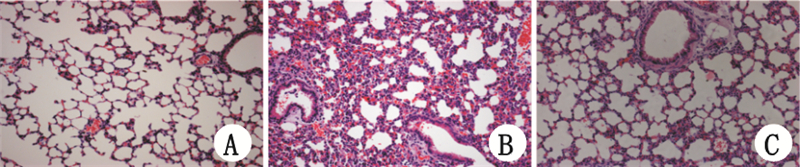

对照组(图 3A)肺组织结构完整,肺泡大小均匀,肺间隔未见增宽,肺间质未见出血、水肿及炎性细胞浸润;LPS组(图 3B)LPS刺激48 h后肺泡结构破坏,肺泡腔变形,肺泡和肺间质水肿,肺泡腔内可见淡红色浆液及炎性细胞浸润;inhibitor+LPS组(图 3C) LPS刺激48 h后肺组织炎性细胞浸润、渗出等病理损伤程度轻于LPS组。

![]() |

| 图 3 光镜下观察各组小鼠48 h肺组织病理变化(HE×20) Fig 3 Pathological changes of the lung tissues in different groups at 48h(HE, ×20) |